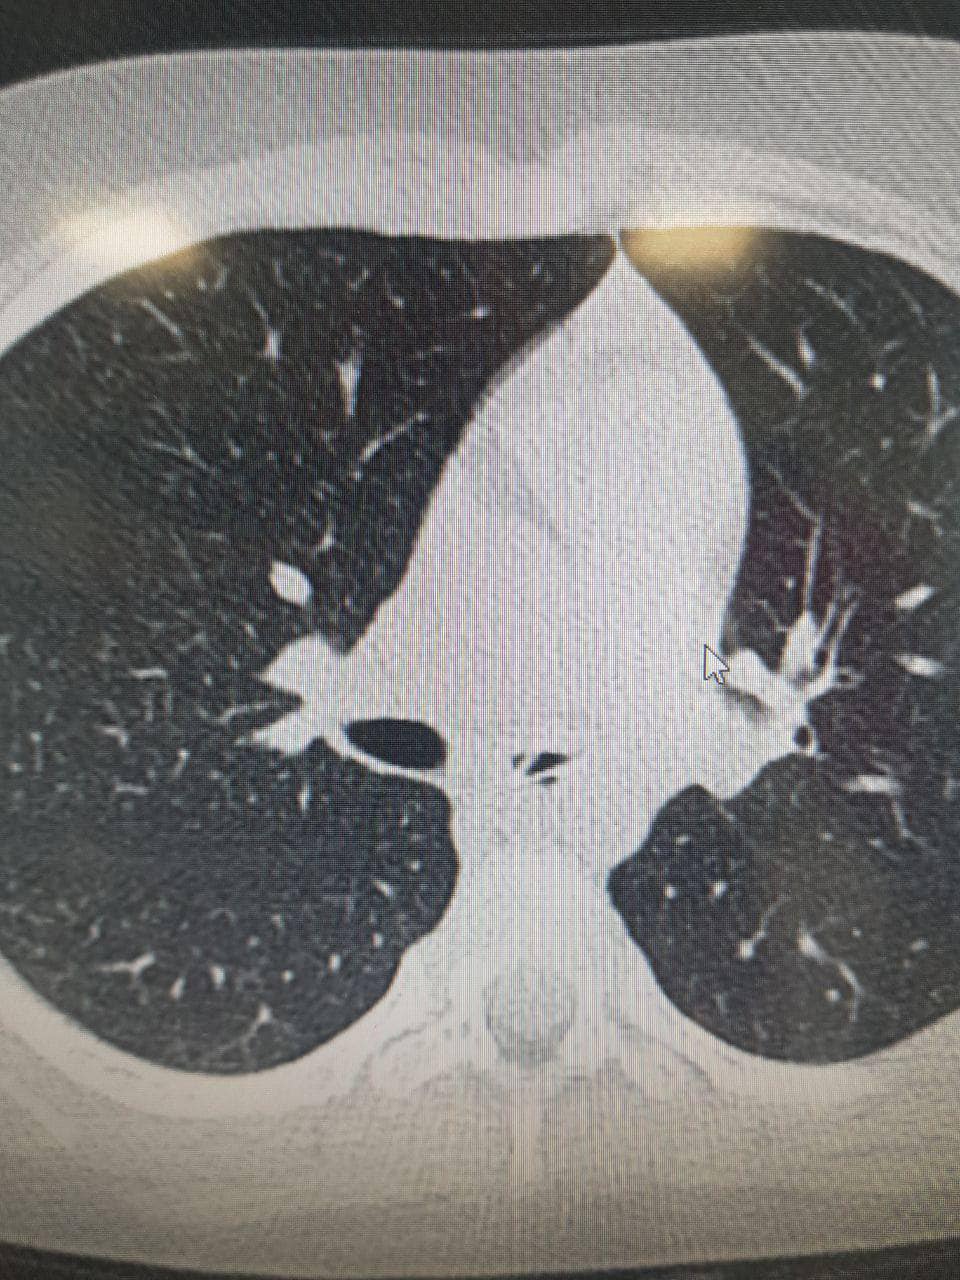

Там лікарі під час обстеження виявили чужорідний предмет у дихальних шляхах дівчинки. Пізніше виявилось, що цим предметом була пластикова ложечка завдовжки 4 сантиметри.

"Нетиповим було розміщення ложечки в лівому бронху. Адже майже завжди сторонні предмети потрапляють у правий бік. Також здивувало те, що дівчинці 6 років, - зазвичай подібні випадки трапляються з дітками віком до 3 років", - розповів Сергій Руденко, завідувач відділення педіатрії.